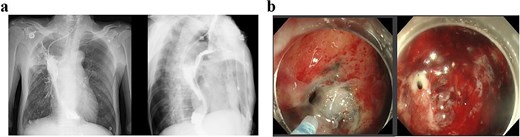

A concise illustration of the disease progression is presented in Fig. 1. A 67-year-old male underwent minimally invasive Ivor Lewis esophagectomy on Day 0, with postoperative confirmation of midesophageal squamous cell carcinoma (T1bN1M0). Follow-up imaging 1 week postsurgery showed no complications (Fig. 2). The patient resumed oral intake without discomfort and was discharged on Day 54.

Upper gastrointestinal series performed during postoperative week 1.